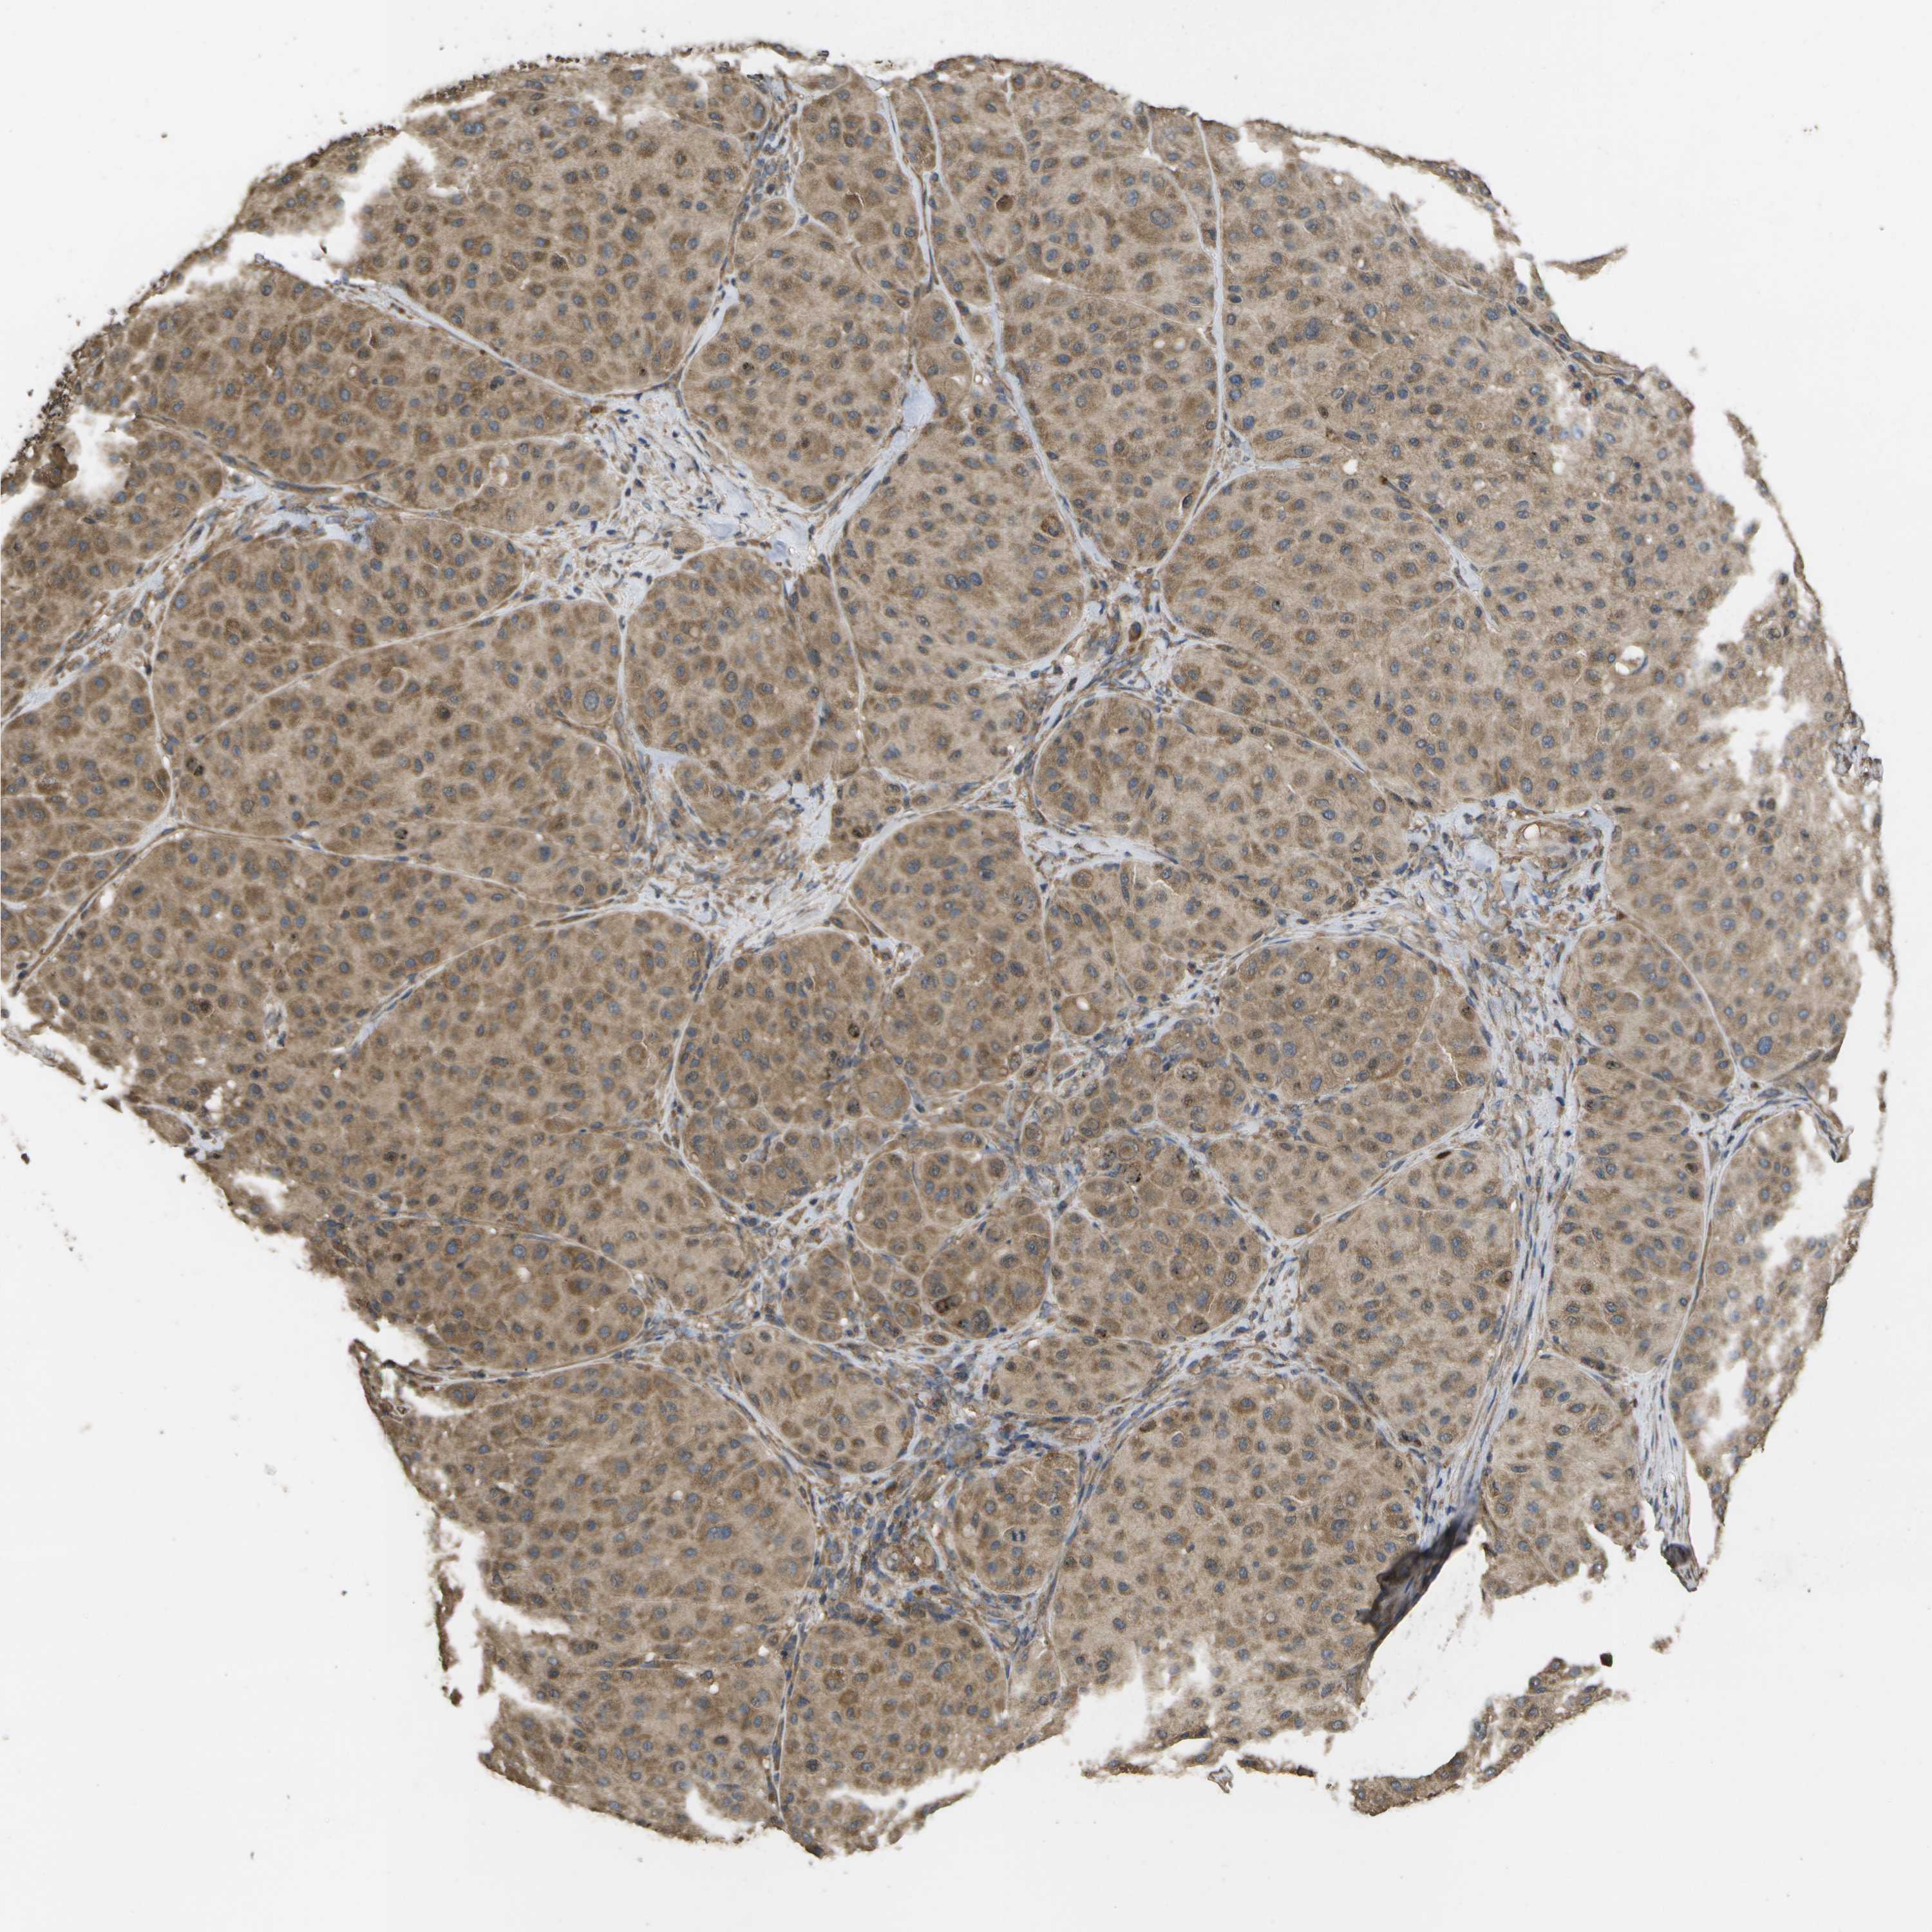

MELANOMA - Protein expressioni

A mouse-over function shows sample information and annotation data. Click on an image to view it in a full screen mode. Samples can be filtered based on level of antibody staining by selecting one or several of the following categories: high, medium, low and not detected. The assay and annotation is described here.

Note that samples used for immunohistochemistry by the Human Protein Atlas do not correspond to samples in the TCGA dataset.

Antibody stainingi

Antibody staining in the annotated cell types in the current human tissue is reported as not detected, low, medium, or high, based on conventional immunohistochemistry profiling in selected tissues. This score is based on the combination of the staining intensity and fraction of stained cells.

Each image is clickable and will lead to virtual microscopy that enables deeper exploration of all samples and also displays staining intensity scores, fraction scores and subcellular localization as well as patient and tissue information for each sample.

Antibody CAB017714

Staining

High

Medium

Low

Not detected

Intensity

Strong

Moderate

Weak

Negative

Quantity

>75%

75%-25%

<25%

None

Location

Nuclear

Cytoplasmic/membranous

Cytoplasmic/membranous,nuclear

Malignant melanoma, NOS

Malignant melanoma, Metastatic site